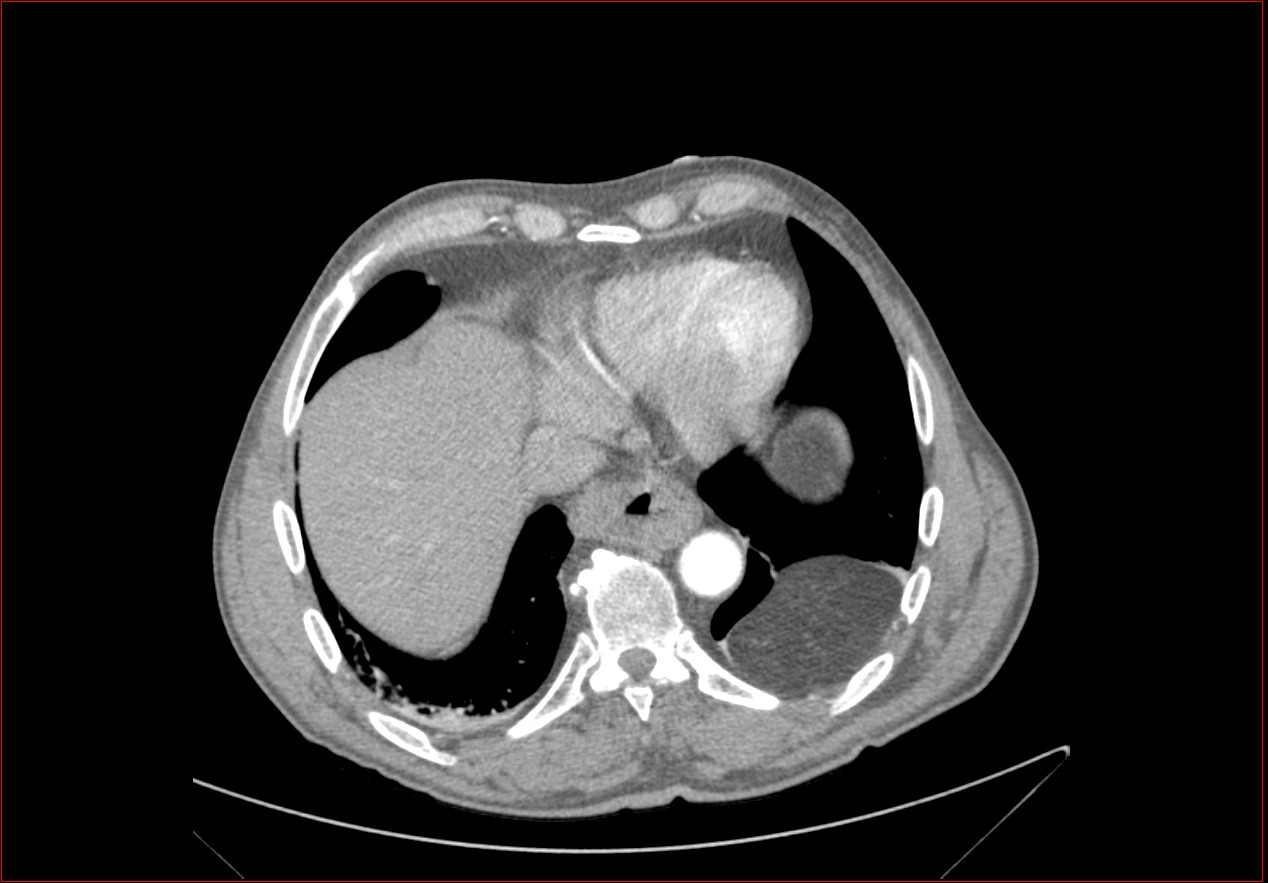

La hernie de Bochdalek est une hernie due à la persistance du canal pleuropéritonéale ce qui aboutit à un hiatus (orifice) dans la partie située en arrière et sur le côté du diaphragme.

La hernie de Bochdalek est plus fréquente à gauche de l’organisme qu’à droite, ceci grâce au foie qui joue un rôle de protection du côté droit.